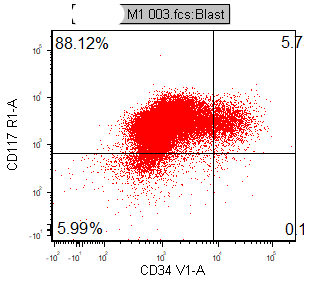

CD41, CD61, CD42b, CD34, CD36, factor VIII and von Willebrand factor

Variable CD13, CD33, CD71, alpha naphthyl acetate esterase, PAS and HLA-DR

Negative stains: Myeloperoxidase, Sudan Black B, CD14, CD64 and glycophorin A.